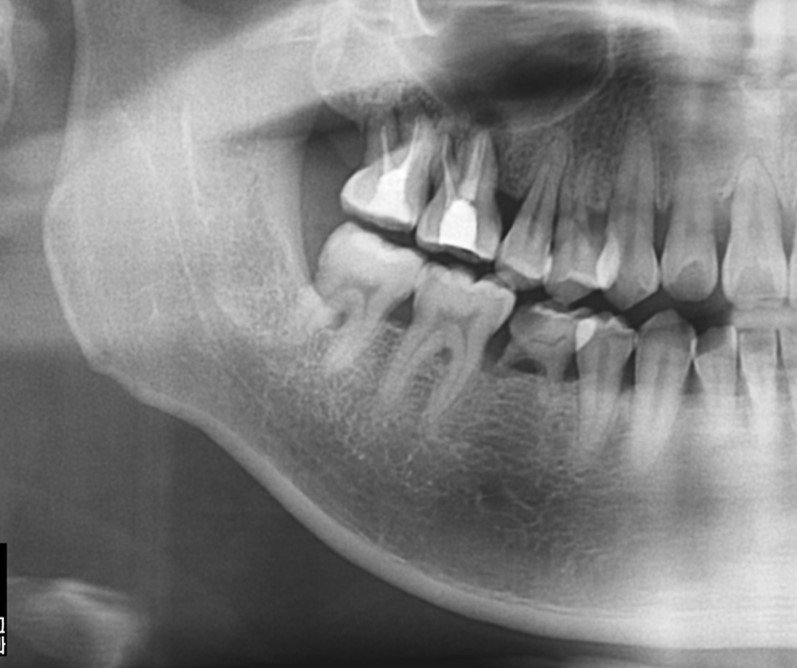

▲Remaining promary tooth